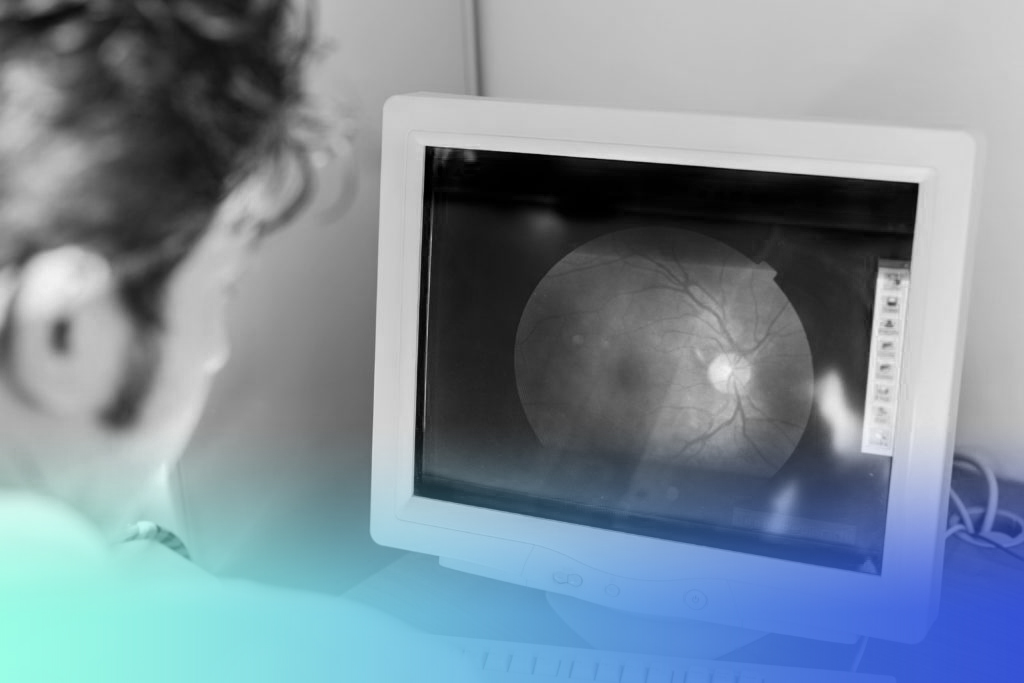

El desprendimiento de la retina es un problema ocular grave, pero ¿qué sucede en el ojo cuando esto ocurre?

Verás, la pared del ojo se compone de tres capas. Hay una interna llamada retina, una intermedia llamada coroides y una externa llamada esclerótica.

El desprendimiento de retina ocurre cuando la misma se separa de la siguiente capa, la coroides. Cuando esto sucede, en el espacio que queda entre ambas, empieza a acumularse líquido.

La retina es la que percibe la luz y le manda las imágenes al cerebro. Gracias a ella, podemos, por ejemplo, hacer actividades como leer o conducir. También nos permite ver todos los detalles que nos rodean, ya que nos proporciona una visión nítida y central. Por lo que un buen estado de esta capa ocular resulta de gran importancia.